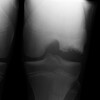

Q

What sign is shown in the elbow if a fracture is present?

A

SAIL sign